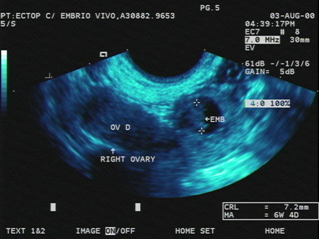

Đối tượng lý tưởng – Các đối tượng lý tưởng với điều trị thai ngoài tử cung bằng MTX là những bệnh nhân có huyết động ổn định, muốn và có thể tuân thủ quá trình theo dõi sau điều trị, có nồng độ β-hCG ≤5000 mIU/mL, và không có hoạt động tim thai. Kích thước khối thai ngoài nhỏ hơn 3-4 cm cũng là một tiêu chuẩn thường dùng để lựa chọn bệnh nhân; tuy nhiên, nó không được xác nhận là một yếu tố dự báo điều trị thành công.

- · Hoạt động tim thai - Sự hiện diện hoạt động tim thai là một chống chỉ định tương đối khác trong điều trị nội khoa [3,12]. Theo một phân tích gộp, bằng chứng của hoạt động tim thai trên siêu âm liên quan có ý nghĩa với thất bại điều trị (OR 9.1, 95% CI 3.8-22.0) [3].

- · Kích thước khối thai ngoài tử cung lớn – Mặc dù kích thước lớn của thai ngoài tử cung (≥3.5 cm) thường được dùng như là tiêu chuẩn để loại trừ trong các phác đồ điều trị nội khoa, sự giới hạn này chỉ dựa trên những nghiên cứu nhỏ với các phác đồ và kết quả điều trị không hằng định [12-15]. Các nghiên cứu đã giới hạn chỉ sử dụng MTX ở những phụ nữ có thai ngoài tử cung nhỏ hơn 3 đến 4 cm [12,13], vì vậy có ít nghiên cứu trên các thai ngoài có kích thước lớn hơn [16]. Ví dụ, một nghiên cứu quan sát phát hiện rằng tỉ lệ thành công của việc điều trị MTX toàn thân cao hơn ở những phụ nữ có khối thai ngoài nhỏ hơn 3.5cm so với những khối có kích thước từ 3.5 đến 4 cm (93% so với 90%) [13].

- · Dịch màng bụng - Kết quả siêu âm của dịch màng bụng tự do là một tiêu chuẩn loại trừ khác cũng được sử dụng thường xuyên trong điều trị thai ngoài tử cung với MTX. Dịch màng bụng có thể là máu, tuy nhiên, đây không phải là chẩn đoán vỡ vòi trứng; máu màng bụng cũng có thể do sẩy thai tại vòi trứng. Về mặt lịch sử, máu tìm thấy qua chọc hút túi cùng trong khoang màng bụng có ở 70 đến 83% phụ nữ có thai ngoài tử cung, nhưng chỉ 50 đến 62% bị vỡ ống dẫn trứng [18-20].